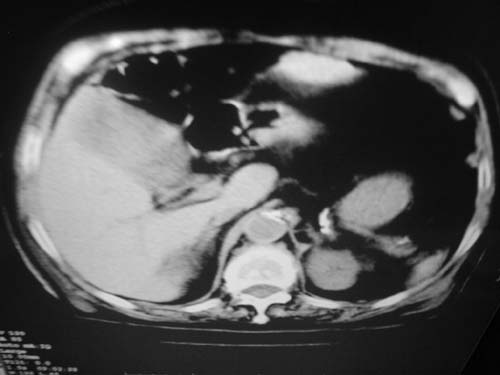

以下是引用余辉在2009-3-11 21:12:00的发言:[br]1肝脾多发钙化结节2右肾结石,右肾积水

以下是引用jiangjing在2009-3-12 17:05:00的发言:[br]1肝脾多发钙化结节2右肾结石,右肾积水 3胆囊炎[br] [br] 左肾囊肿